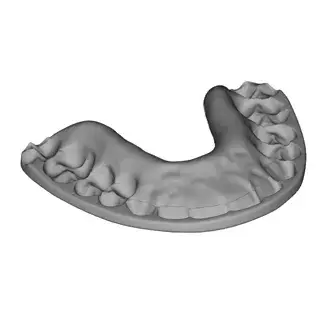

3D Systems' VSP® surgical planning solutions for craniomaxillofacial (CMF) applications received FDA clearance as a service-based approach to personalized surgery over 10 years ago.

3D Systems and Stryker Corporation have partnered to provide surgeons with best-in-class products and services for craniomaxillofacial surgeries. As a leader in personalized healthcare solutions, 3D Systems has planned and delivered devices for more than 140,000 patient-specific cases. The Stryker Craniomaxillofacial business specializes in providing patient-specific options and innovative solutions that help drive efficiencies in surgical suites. The combination of Stryker’s specialized team and advanced implants with 3D Systems' cutting-edge 3D printing technologies and expert consulting services positions both companies to provide a superior level of service to healthcare professionals who use these revolutionary solutions.